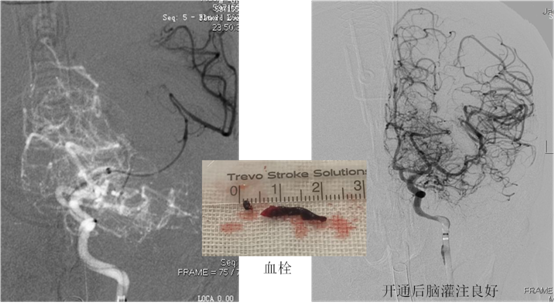

方案已定,笃定精神,“先将血压维持在120-130mmHg之间”,主刀医生对麻醉医师说,这是为了在血管开通之前让脑细胞保持足够的血供防止脑损伤进一步加重,导丝巧妙通过狭窄,交换导引导管缓慢的通过狭窄处进入颈内动脉远端(此处全靠手法),万里长征第一步成功迈出。抽吸导管到达血栓近端,取栓微导管越过血栓到达远端造影显示远端血管通畅,取栓支架释放,取栓支架连同抽吸导管合力吸除大脑中动脉血栓,两次取栓颅内血管完好再通,取出约1.5cm长红黑色质韧血栓,万里长征已走完一半,大家心里都松了一口气,可是主刀陈仁彪医师一点也不敢松懈,因为还有一个大麻烦等在后面,颈动脉狭窄的安全处理以及血管全部开通后的脑组织再灌注损伤在等着。

“麻醉医师帮忙降血压,维持在110-120mmHg之间”,这是主刀医师第二次与麻醉医师交流,大家都聚精会神,血压平稳下降并维持,进保护伞(防止颈动脉狭窄近端残留血栓再次脱落至脑内),球囊依次扩张颈动脉狭窄处,植入颈动脉支架,回收保护伞(伞内可见血栓,可见保护伞的重要性),造影显示支架形态良好,血流通畅,颅内灌注良好,心率、血压平稳,3D-CT显示颅内未见出血,将患者平安转入ICU后大家抬头看时间已是凌晨两点半,术后24小时患者清醒拔管,对答切题,双侧肢体肌力基本恢复。